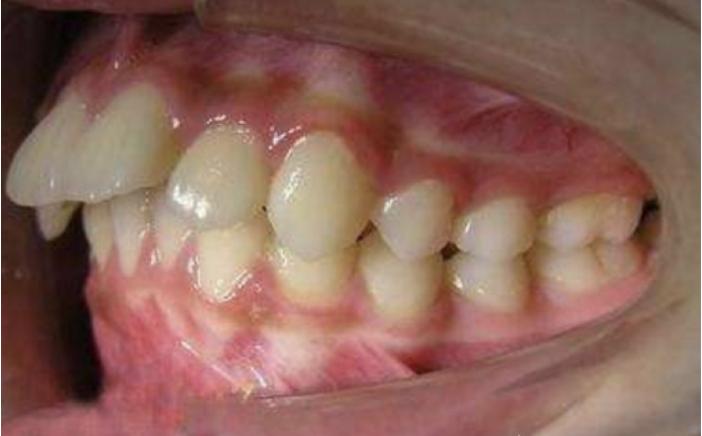

牙齿“飞出去”造成龅牙